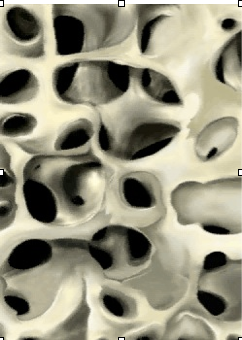

Osteoporosis is a disorder of skeletal insufficiency that is typically a result of increased bone breakdown relative to bone formation. With aging and in women the transition to menopause, the rate of bone loss accelerates. Over time, the thinning of the bone creates a more fragile skeleton that is susceptible to fracture.